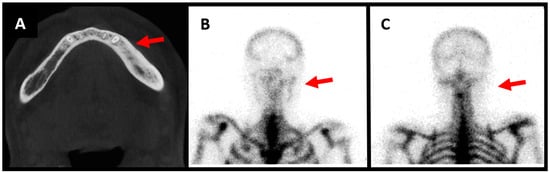

Figure 1. Male patient aged 57 years old, presenting with left mandibular pain associated with swelling ongoing for 1 year. He underwent extraction of tooth 35 prior to the pain. He notices improvement of the pain with nonsteroidal anti-inflammatory drugs, but recurrence of pain and swelling as soon as he stops medication. No infectious symptomatology is described by the patient and on clinical evaluation we notice no infectious signs and no hypoesthesia of the mandibular nerve. Surgical biopsy shows bone neoformation and fibrous reorganization. There is no inflammatory syndrome in laboratory results. CT scan demonstrates osteocondensation with aspects of sclerotic bone ((A), red arrow). The three-phase osseous scintigraphy shows alteration in the three phases, with hyperfixation of the tracer on the left mandibular horizontal bone compatible with a diagnosis of osteomyelitis ((B), red arrow). The scintigraphy with anti-granulocytes antibodies shows no hyperfixation of the antibodies in either early or late images, thus excluding an infectious osteomyelitis ((C), red arrow). The symptoms resolved after long-term treatment with nonsteroidal anti-inflammatory drugs.